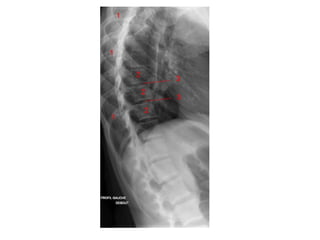

INCIDÊNCIAS ESCOLIOSE

COLUNA TOTAL ESCOLIOSE